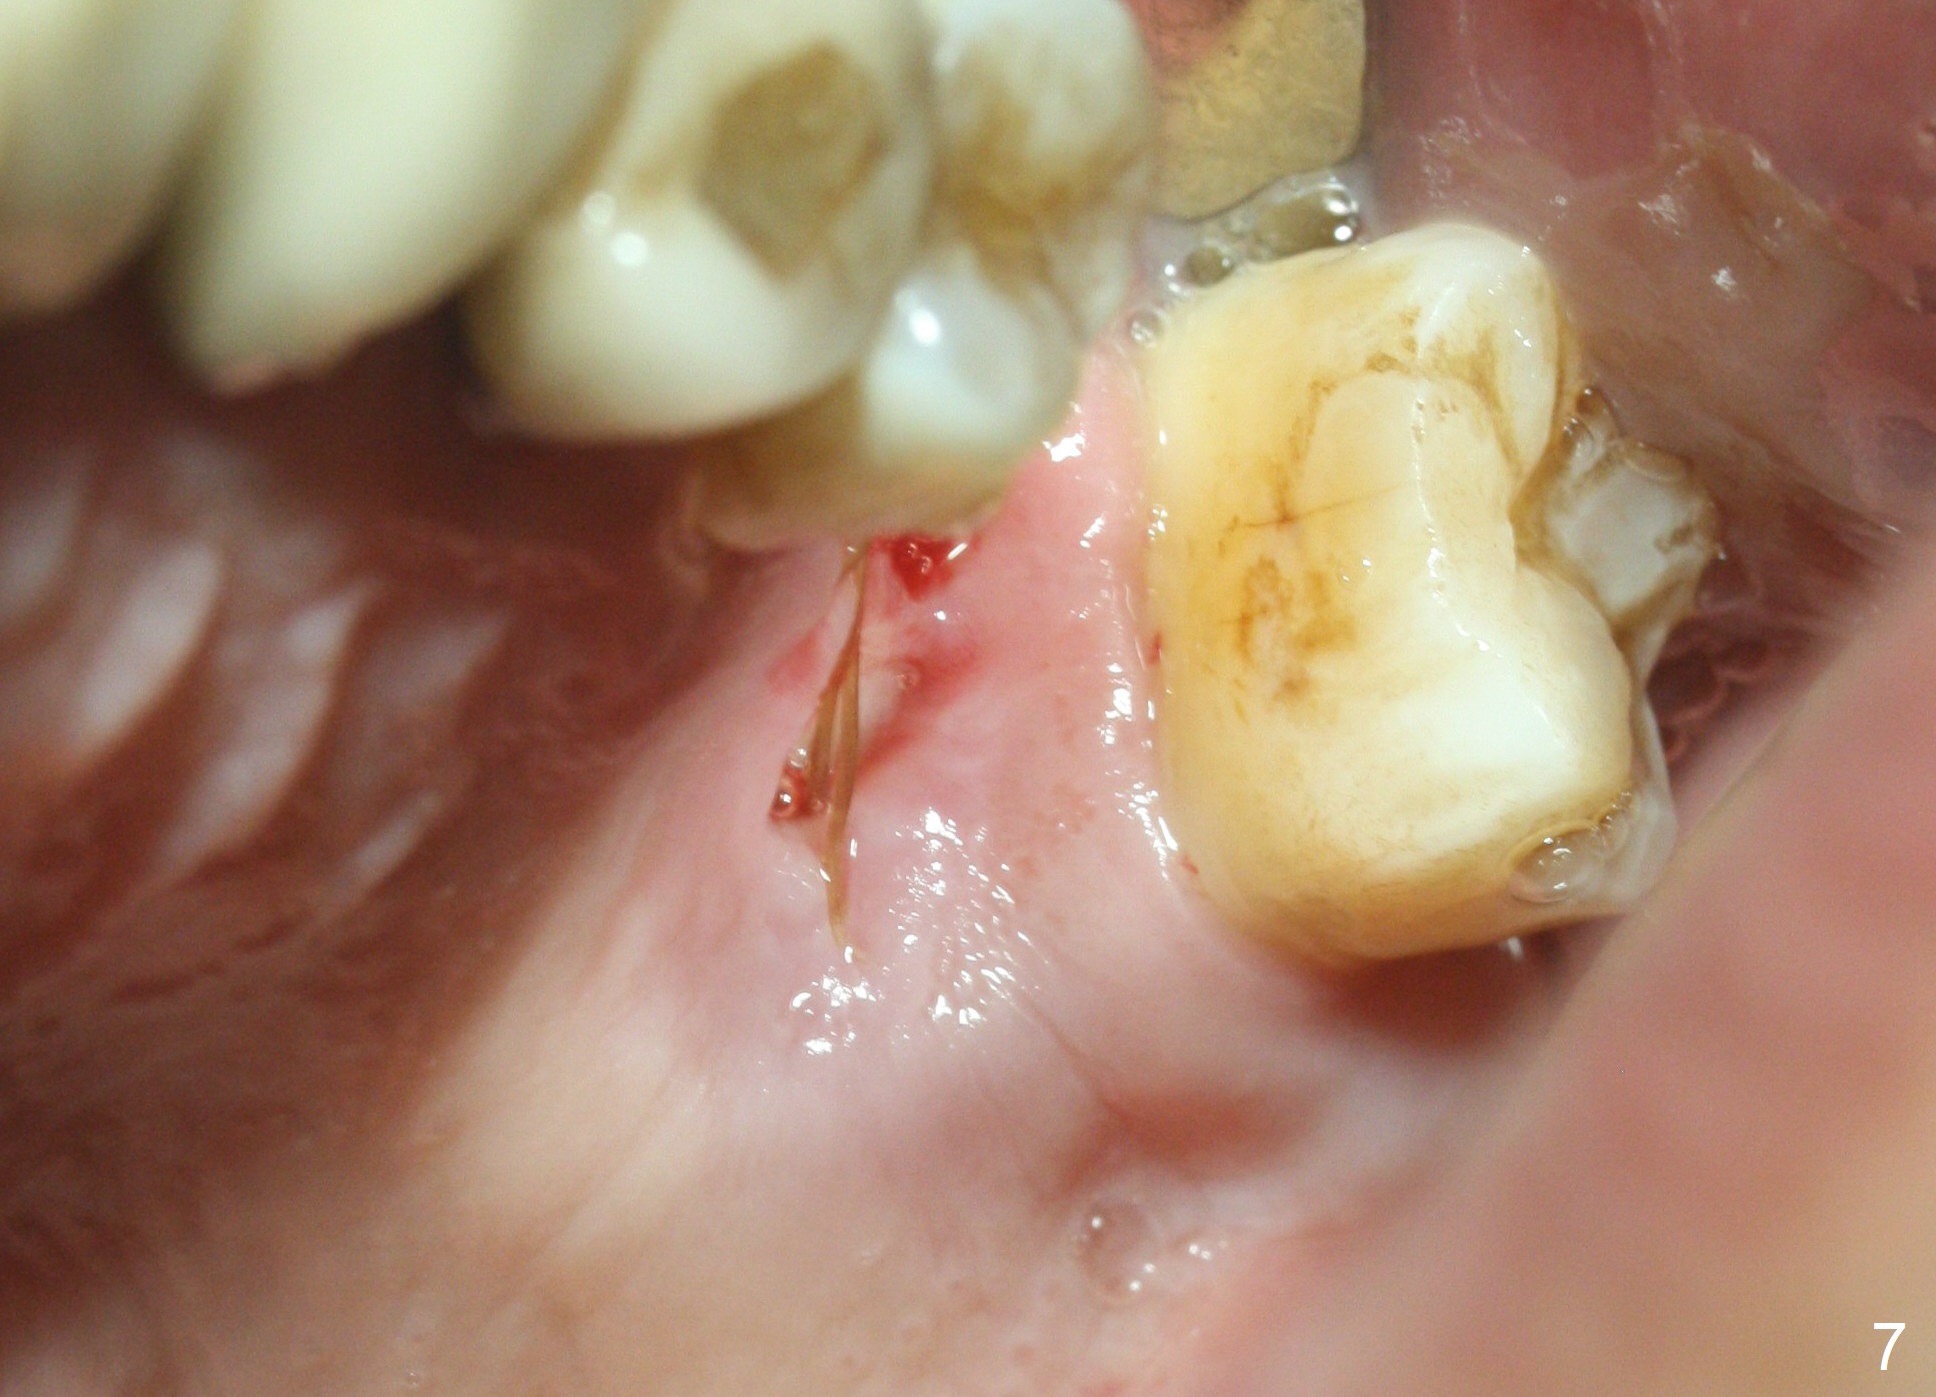

When the tooth #14 is extracted, the buccal plate is lost, while the apex of the palatal socket is perforated. The palatal slope of the septum appears to be a suitable site for osteotomy, but the depth seems to be 2 mm. After sequential osteotomy until 5.3 mm with drills, a 5.9 mm SM tap obtains stability (Fig.2). A 5.9x8 mmm implant is placed with barely sufficient stability after 1 piece of PRF membrane and VeraGraft (Fig.2-4). The implant rotates and dislodges when an abutment is being placed. Neither do 6-8x17 mm Tatum taps achieve primary stability. Socket preservation is performed, followed by periodontal dressing (Fig.5). Primary stability might have been obtained if a smaller IBS implant with fins were placed in the palatal socket. The periodontal dressing has dislodged 1 week postop; the socket appears healing (Fig.6,7). Bone graft seems to be minimal or bone density of the graft is low (Fig.8). The socket heals with a wide ridge 2 months post socket preservation, but the tooth #15 seems to be buccal (Fig.9) and mesial (Fig.10) shift. After use of Magic Split and Expanders (until 3.8 mm for 13 mm), try 5 mm dummy implant (Fig.11). If 6 mm one fails to achieve stability substantially, switch to 7 mm Tatum tapered tap provided there is enough mesiodistal space (use 8 mm implant positioner to gauze the space beforehand (preop)). Consider using Vanilla (not Vera) Graft to fill in the gap between implant and osteotomy. When primary stability is obtained, place a nonfunctional provisional to prevent further shifting (Fig.11 white outline). After osteointegration, use the provisional (reline and separator) to distalize the tooth #15.